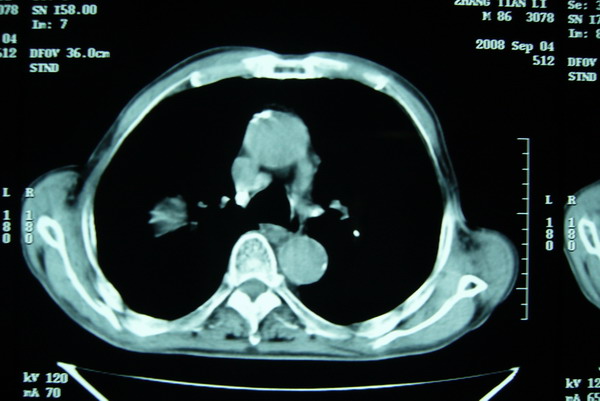

标题: CT15579:男 86岁 咳嗽 咳少量白痰 发热2天 吸烟史60年 [打印本页]

标题: CT15579:男 86岁 咳嗽 咳少量白痰 发热2天 吸烟史60年

右肺上叶巨大软组织肿块,轮廓不规则,纵隔内有肿大淋巴结,首先考虑肺癌。

右上肺一不规则团块,边缘有分叶和毛刺,纵隔有淋巴结肿大。右肺周围性肺癌首先考虑。